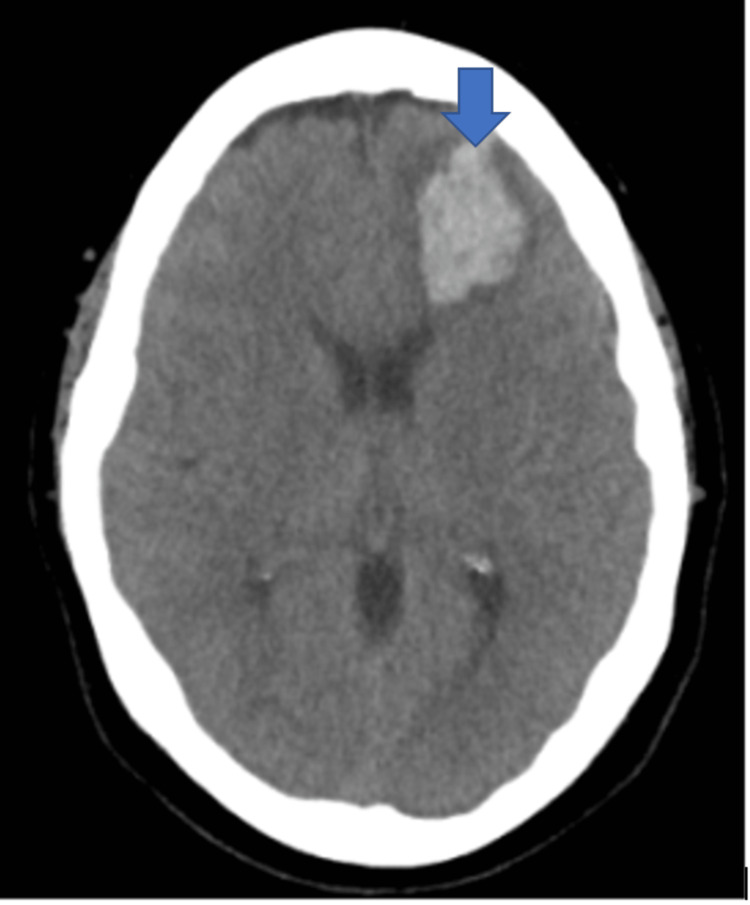

A year after her last outpatient appointment, she presented to the hospital with recurrent episodic thunderclap headaches with associated nausea, vomiting, and photosensitivity. Her neurologic examination was notable for aphasia without notable weakness. In the interim, she had established care with another neurologist who was closer to her home, who had discontinued verapamil and started the patient on venlafaxine for treatment of headaches and mood. CT Head without contrast revealed bilateral SAHs and a left frontal intraparenchymal hemorrhage, approximately 9.4 cc by ABC/2 formula (Figure 3). CTA Head and Neck with contrast again demonstrated multifocal stenosis of intracranial arteries. She underwent a second DSA, which demonstrated multifocal stenosis of intracranial arteries bilaterally (Figures 4–5). Angiogram found diffuse irregularities primarily affecting bilateral anterior cerebral arteries and, to a lesser extent, the bilateral middle cerebral and right superior cerebellar arteries. The patient also underwent brain biopsy with hematoma evacuation. Rheumatological workup was repeated and unremarkable. Lumbar puncture was performed and notable for mildly elevated glucose of 85 (normal range: 50-75 mg/dL) and mildly elevated protein at 46 (normal range: 15-45 mg/dL). Due to concern for PACNS as per discretion of treating physician at that time given the recurrence of symptoms and vascular irregularities, she was administered one dose of high-dose IV methylprednisolone, but this was discontinued when brain biopsy was planned. The biopsied temporal artery, dura, and brain showed no evidence of vasculitis. In the absence of any evidence for an ongoing inflammatory process, verapamil was restarted for symptomatic treatment of suspected recurrent RCVS. It was felt that RCVS was likely precipitated to exposure to SNRI. Venlafaxine was discontinued as this is a known precipitant of RCVS. After clinical improvement, the patient was discharged home and advised to continue verapamil, follow up with vascular neurology outpatient clinic, and undergo follow-up repeat vessel imaging.

Unfortunately, she returned to the hospital one week later with new onset right facial weakness and receptive aphasia. CT Head without contrast now revealed an acute left temporal lobe hemorrhage approximately 5.5 cc by ABC/2 formula (Figure 6). CTA Head and Neck with contrast demonstrated increased multifocal irregularities compared to prior imaging studies. Patient’s home dose of verapamil was increased. The patient improved clinically and at the time of discharge, she had residual receptive aphasia and trace right facial weakness. There was suspicion that the patient was using medical marijuana for symptomatic relief of headache pain as per collateral obtained from patient’s family. At the time of discharge, the patient was extensively counseled to avoid all possible precipitants of RCVS.